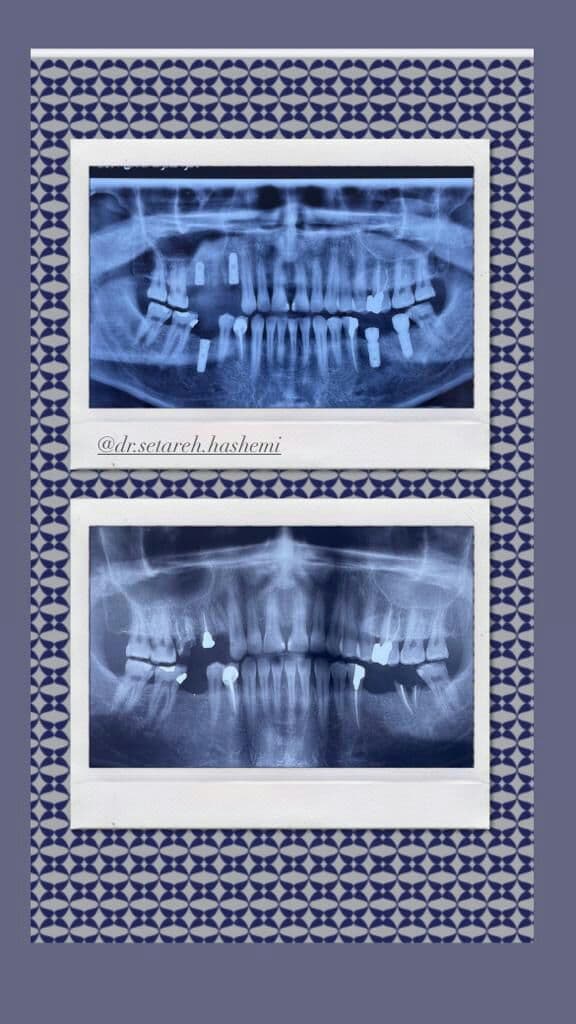

جراحی ایمپلنت های دندانی , پیوند استخوان , جراحی سینوس

در بعضی موارد مراجعه دیرهنگام فرد برای کاشت دندان (ایمپلنت) یا وجود کیست و تومورهای دهانی منجر به از بین رفتن فضای مناسب و کم شدن قطر و ارتفاع استخوان فک میشود که در این حالت، دندانپزشک قبل یا همزمان با جایگذاری فیکسچر، با استفاده از پودر و بلاک استخوانی و ممبرین (بایومتریالها) استخوان را بازسازی کرده تا شرایط مناسب برای قرارگیری ایمپلنت مهیا گردد. در این مواقع طول درمان بیمار (آماده شدن استخوان برای جایگذاری ایمپلنت) بسته به شرایط بیمار از ۳ تا ۶ ماه طول میکشد و دندانپزشک به کمک عکسهای رادیوگرافی میتواند روند درمان را دنبال کند و بهترین زمان را برای کاشت ایمپلنت تشخیص دهد.